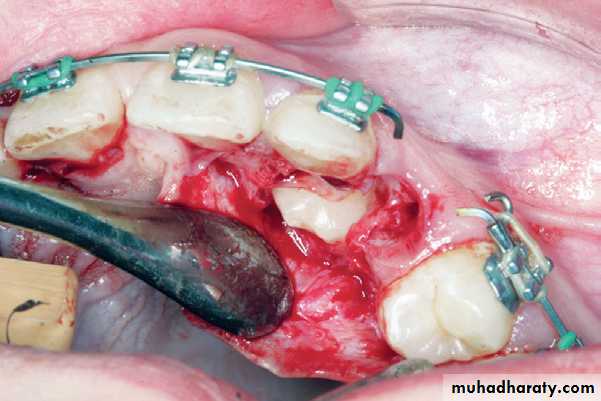

Reflection of the mucoperiosteal flap. Arrow points to the nasopalatine nerve

Removal of the bone covering the crowns of impacted teeth

Palatal impaction canineSurgical field immediately after exposure of

impacted teeth. Orthodontic brackets have been placed on exposed parts of the crowns of the teethSurgical field after suturing